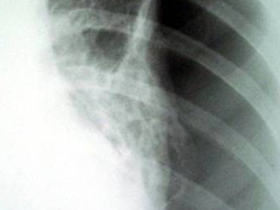

Derrame pleural leitoso (quilotórax)

Pneumotórax à esquerda

Quilotórax à esquerda